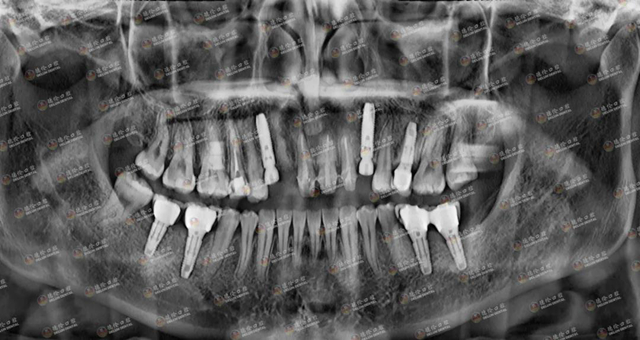

刘女士术后牙片